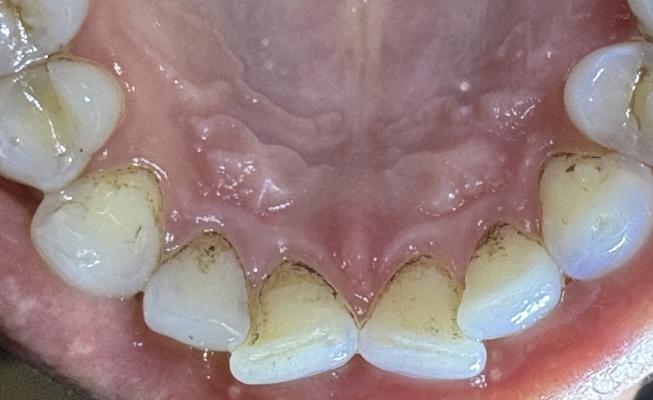

- удаление твердых зубных отложений с помощью ультразвукового скейлера

Метод рекомендован для удаления зубного камня

Фотографии пользователей: